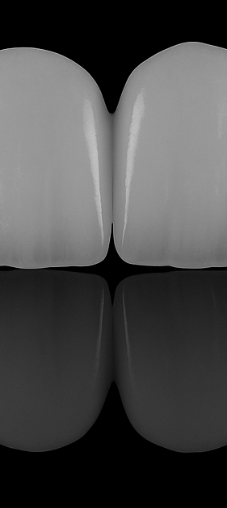

심미보철계의 Ceramist,

국제적인 치과 심미 연구 그룹 오랄디자인 서울 기공소에서 만드는

수제작 라미네이트

얇고 투명한 투과율로 높은 심미성, 높은 강도를 자랑하는 리튬 다이 실리케이트 블럭을

이용하여 적은 치아 삭제로 이상적인 치아를 복원이 가능합니다.

두꺼울수록 치아 삭제량이 많아지는 기존의 방식을 보완한

매우 얇고 치아에 잘 맞는 0.1mm 두께 보철로 자연스러운 라미네이트를 진행합니다.